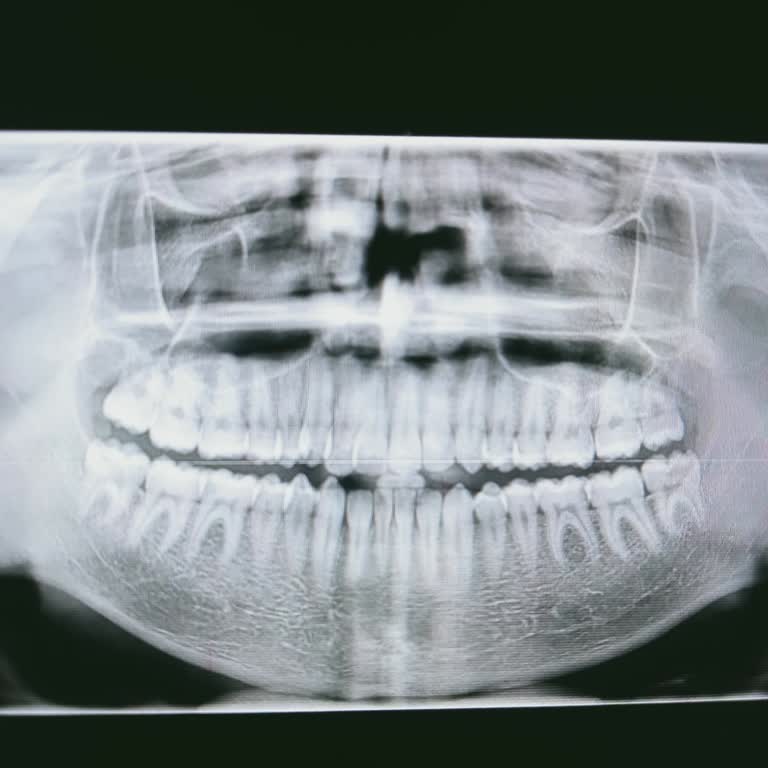

Yaklaşık dört ay önce kızımın tedavisi için Aydın Üniversitesi Diş Hastanesi’ne başladık. Tedavi öncesinde röntgenleri çekildi, yapılacak işlemler söylendi ve 4 dolgu ile diş temizliği için 12 bin tl fiyat verildi. Plak ya da tel için ise net fiyat veremeyeceklerini, 55 bin ile 75 bin tl arasında de...